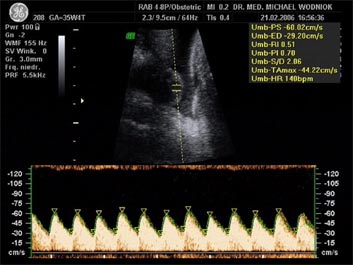

Blutflußmuster (Nabelschnurarterie)

Weitere Ultraschalluntersuchungen sind in der 10./20./30. Schwangerschaftswoche gemäß den Mutterschaftsrichtlinien vorgesehen. Bei erkennbaren Risiken werden  weitere Untersuchungen angeschlossen. Spezielle Ultraschalluntersuchungen zum Ausschluss von kindlichen Entwicklungsstörungen sowie Durchblutungsmessungen der mütterlichen und kindlichen Blutgefäße mittels Farbdopplersonographie gehören zum Leistungsspektrum der Praxis. Auf Wunsch können auch 3D und 4D Untersuchungen angeboten werden.